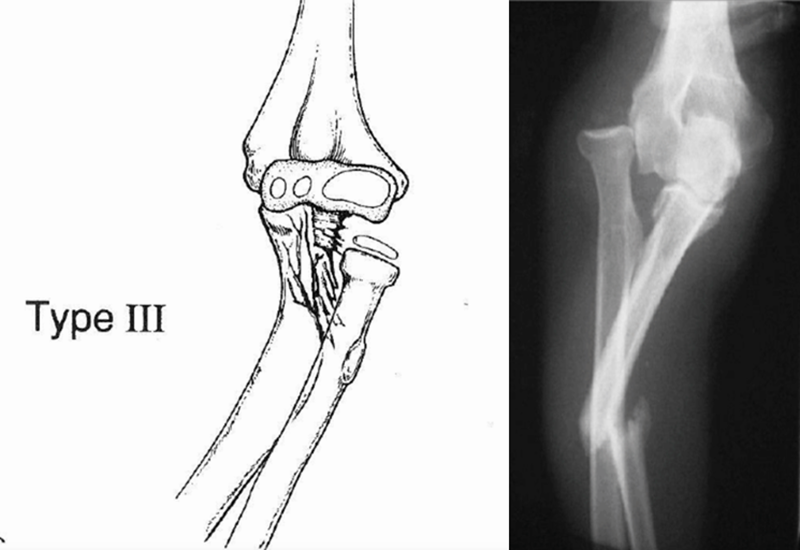

Ⅲ型(内收型):桡骨头后外侧或是前外侧脱位,尺骨近端骨折且可累及干骺端,仅在儿童中发病,又称为儿童型,约占7%~20%。

受伤机制:在肘关节内翻应力的作用下,先造成尺骨近端的青枝骨折,使桡骨头向外侧或前外侧脱出。